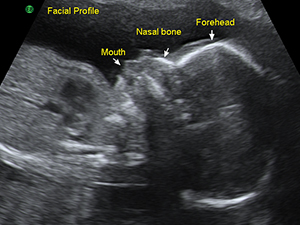

中孕期的側面輪廓

中孕期的鼻子與咀唇